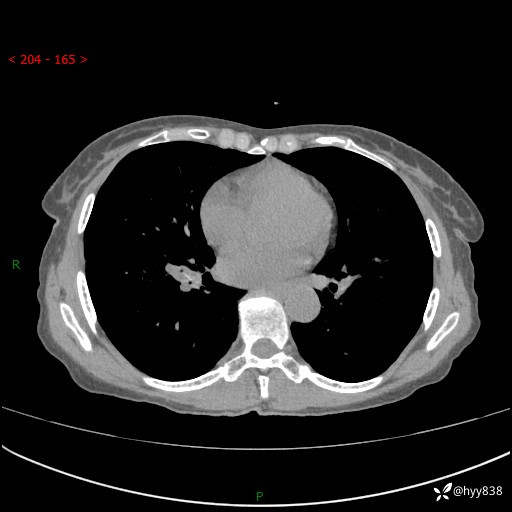

患者性别:男

患者年龄:69岁

简要病史:咳嗽咳痰2月,夜间加重

临床诊断:感染

胸部CT平扫